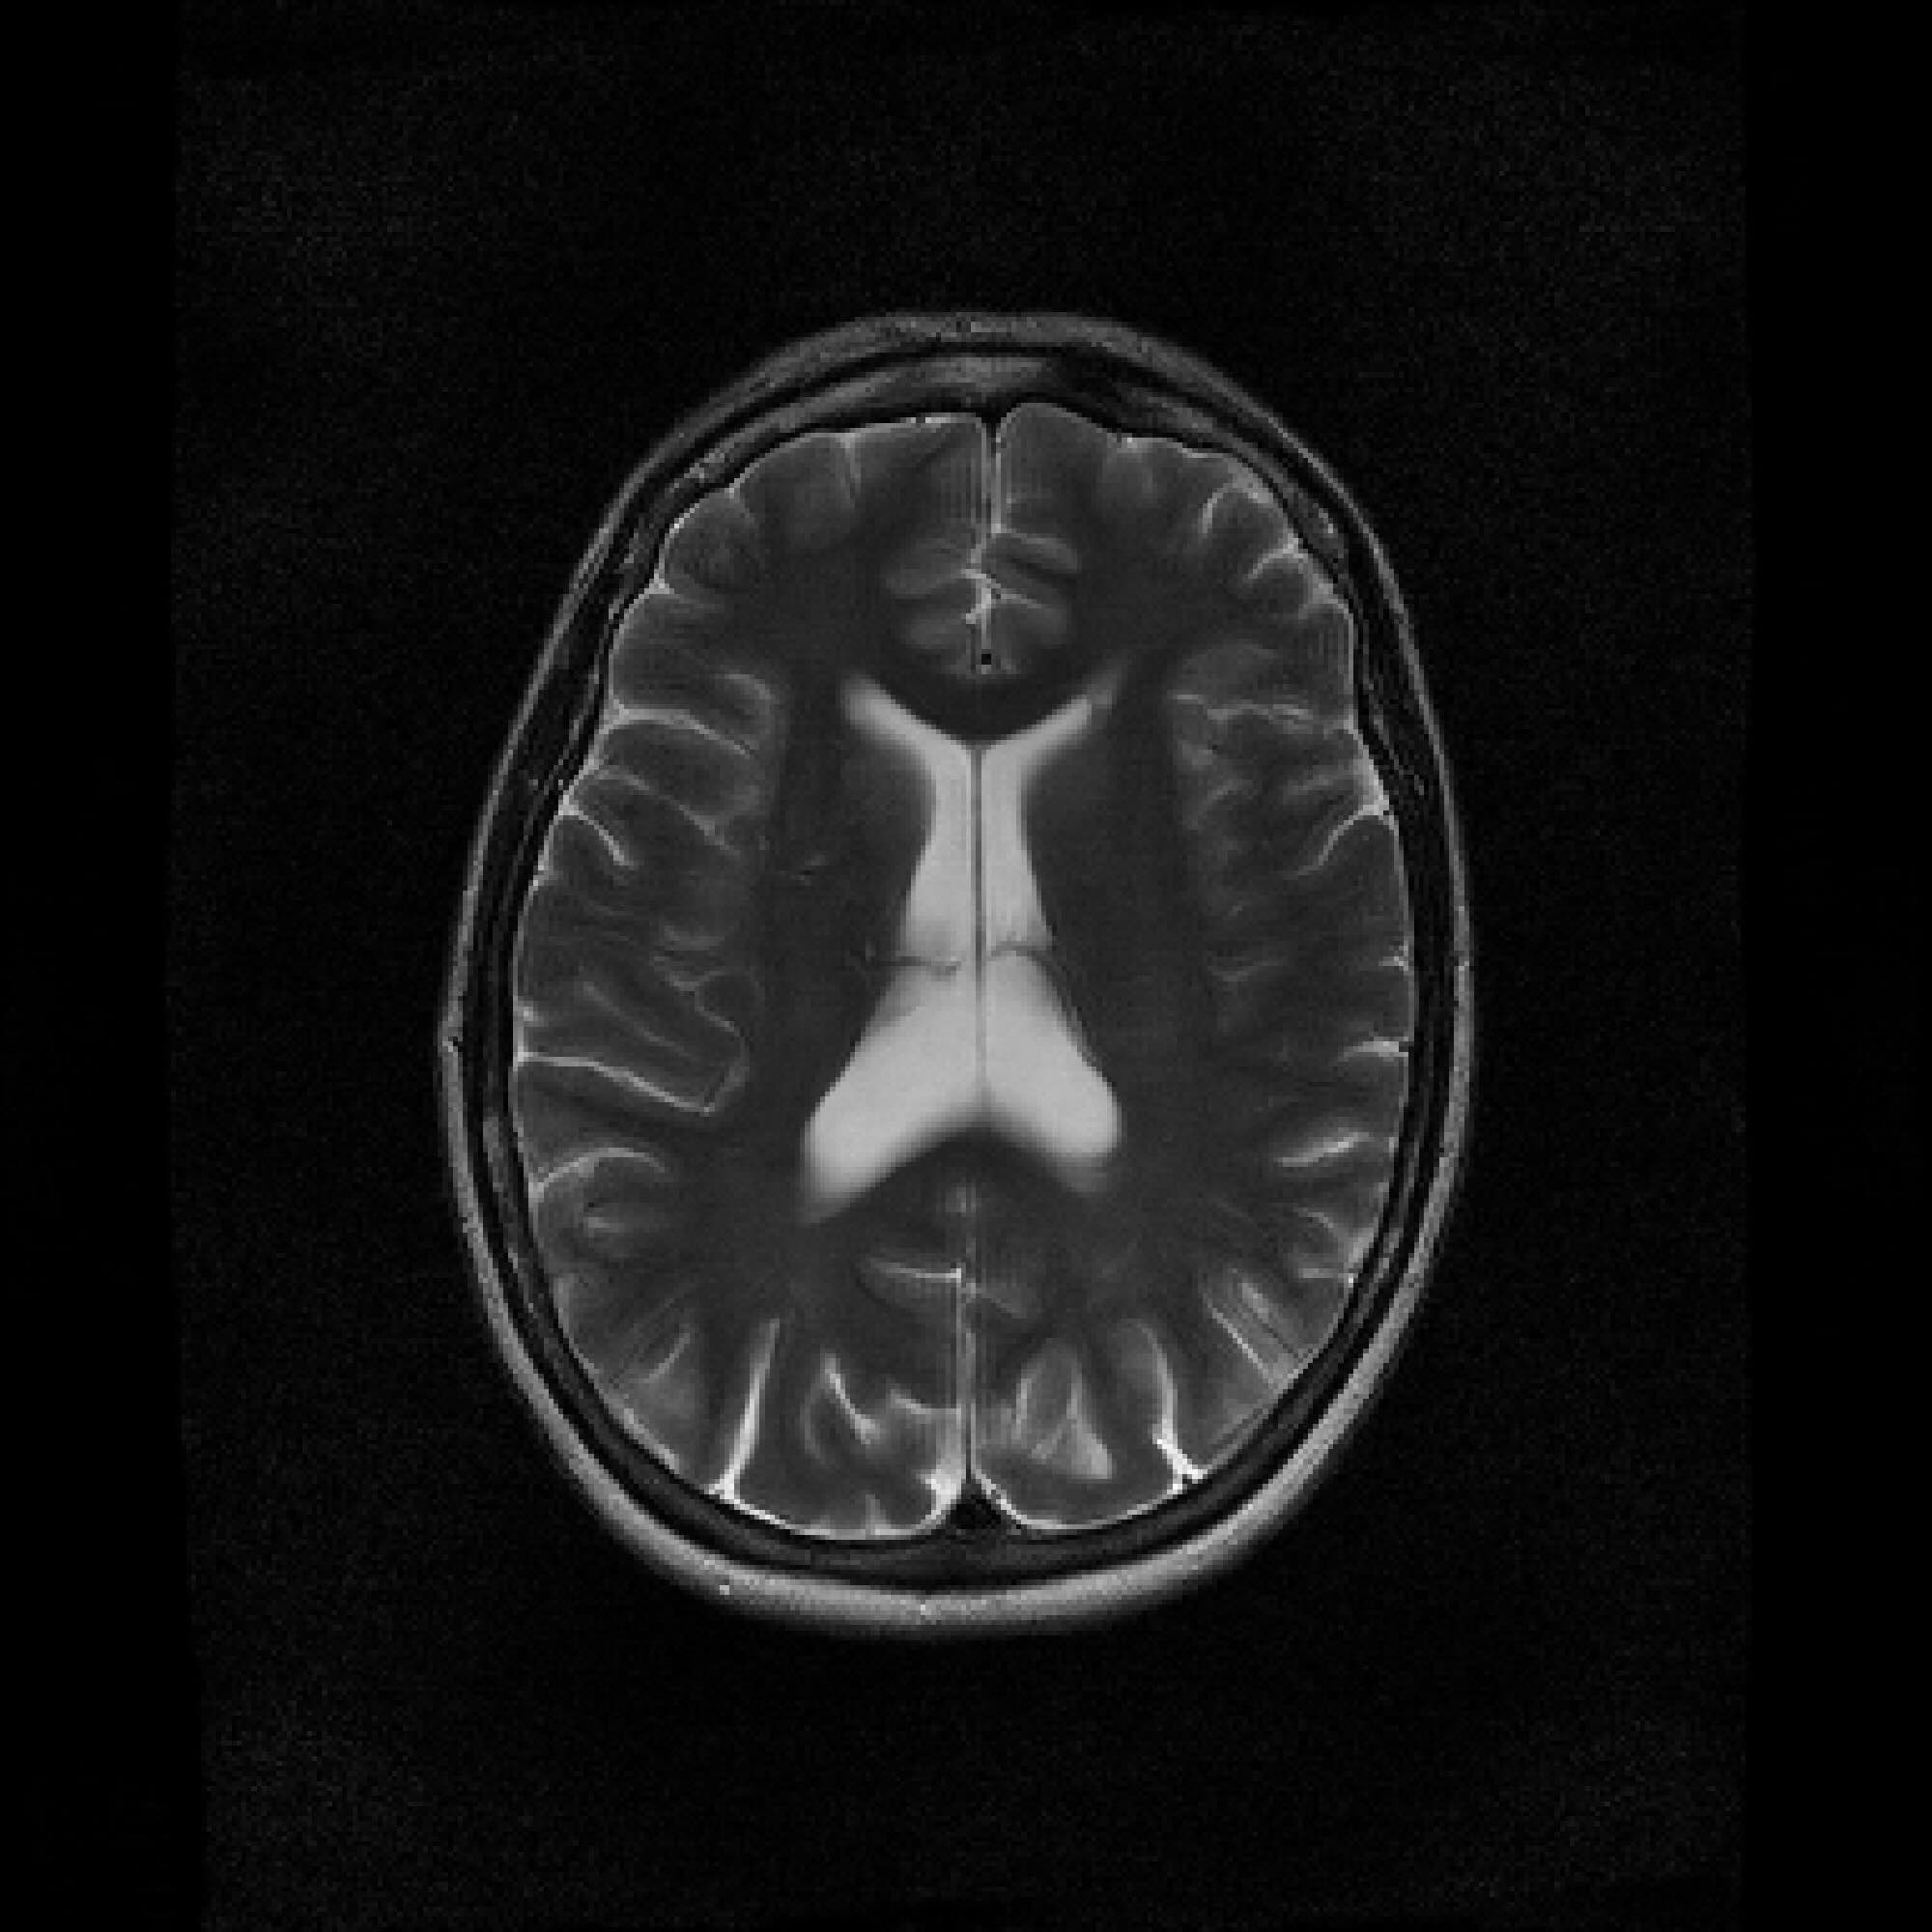

Refer to caption

Figure 2: Example MRI magnitude reconstructions with S=25S=25 training slices at acceleration (undersampling) factor R=7R=7. PaDIS-MRI reconstructions are sharper and more faithful to the fully-sampled ground truth. Insets are shown to the right to highlight detail.

Figure 2 provides a visual comparison of the reconstruction quality of each method on example slices. In reconstructions from the S=25,R=7S=25,R=7 models, FastMRI-EDM exhibits slightly more blurring and loss of fine structural details, particularly in regions with complex anatomical features. PaDIS-MRI, in contrast, preserves sharper boundaries and finer details. This enhanced data efficiency can be attributed to the patch-based prior’s ability to learn localized structural motifs more effectively from limited examples. Figure 6 in the Appendix shows similar reconstructions at S=200,R=7S=200,R=7 where FastMRI-EDM more closely approaches the performance of PaDIS-MRI but still struggles with highly detailed anatomy.